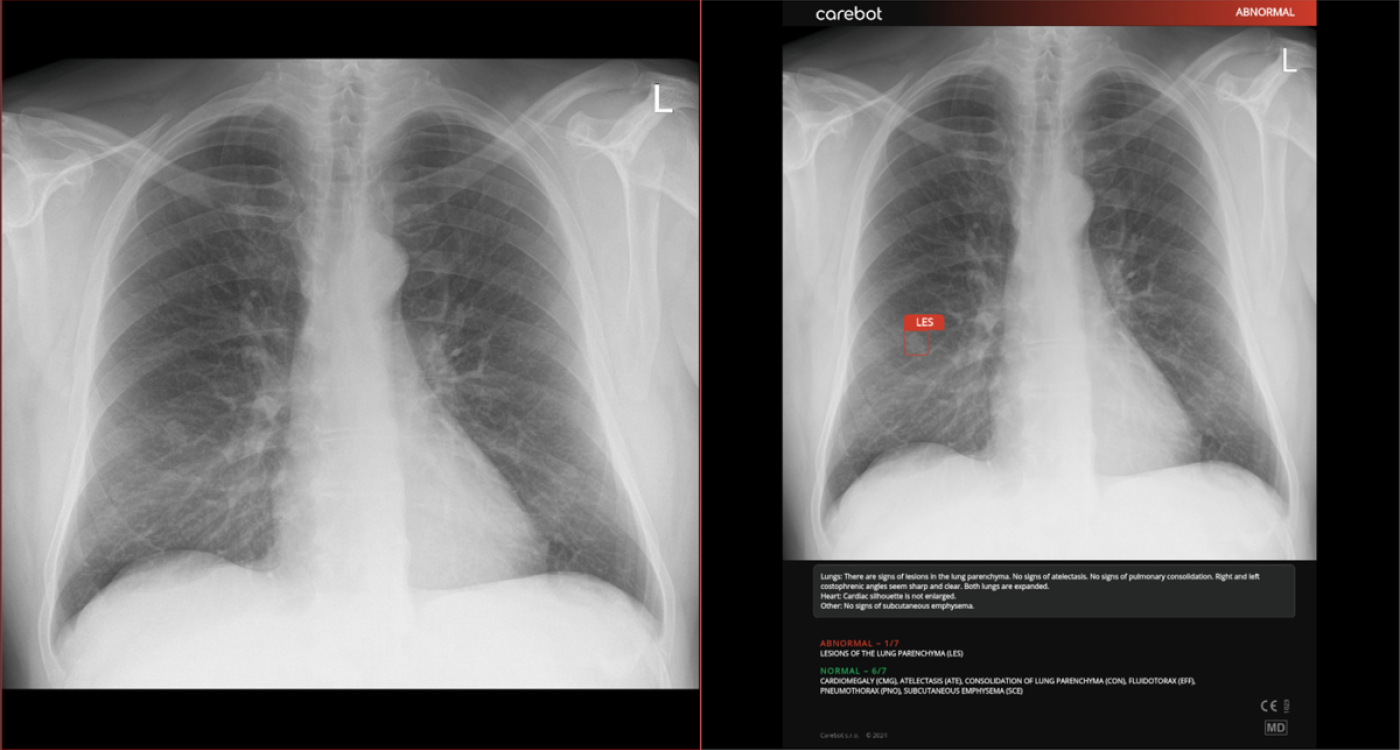

Czech AI company and Bristol Myers Squibb announced a collaboration to improve early detection of lung cancer. This innovative partnership will enable the integration of Carebot, a solution that assists physicians in evaluating X-ray images to increase diagnostic accuracy and accelerate the identification of early-stage lung cancer.

Lung cancer is among the most challenging cancers to detect, with delayed diagnosis often reducing the chances of effective treatment. With Carebot’s artificial intelligence, healthcare professionals can analyze chest X-rays with high accuracy and rapidly identify abnormalities that may indicate early-stage lung cancer. The company’s artificial intelligence, Carebot, holds the potential to analyze thousands of chest X-rays in a fraction of the time required for manual evaluation, which can increase diagnostic accuracy by up to 20% and reduce diagnosis time by up to 30%.

As part of the pilot project, the technology will be rolled out in five selected hospitals in the Czech Republic. Healthcare professionals, accompanied by AI, will evaluate all chest X-rays. “Carebot’s artificial intelligence is implemented directly into the system we commonly use for diagnosis. Less experienced doctors often assess chest X-rays. The AI notifies them of even small lesions that might otherwise be missed,” said Pavel Struna, Head of the Radiology Department at the Slaný Hospital.